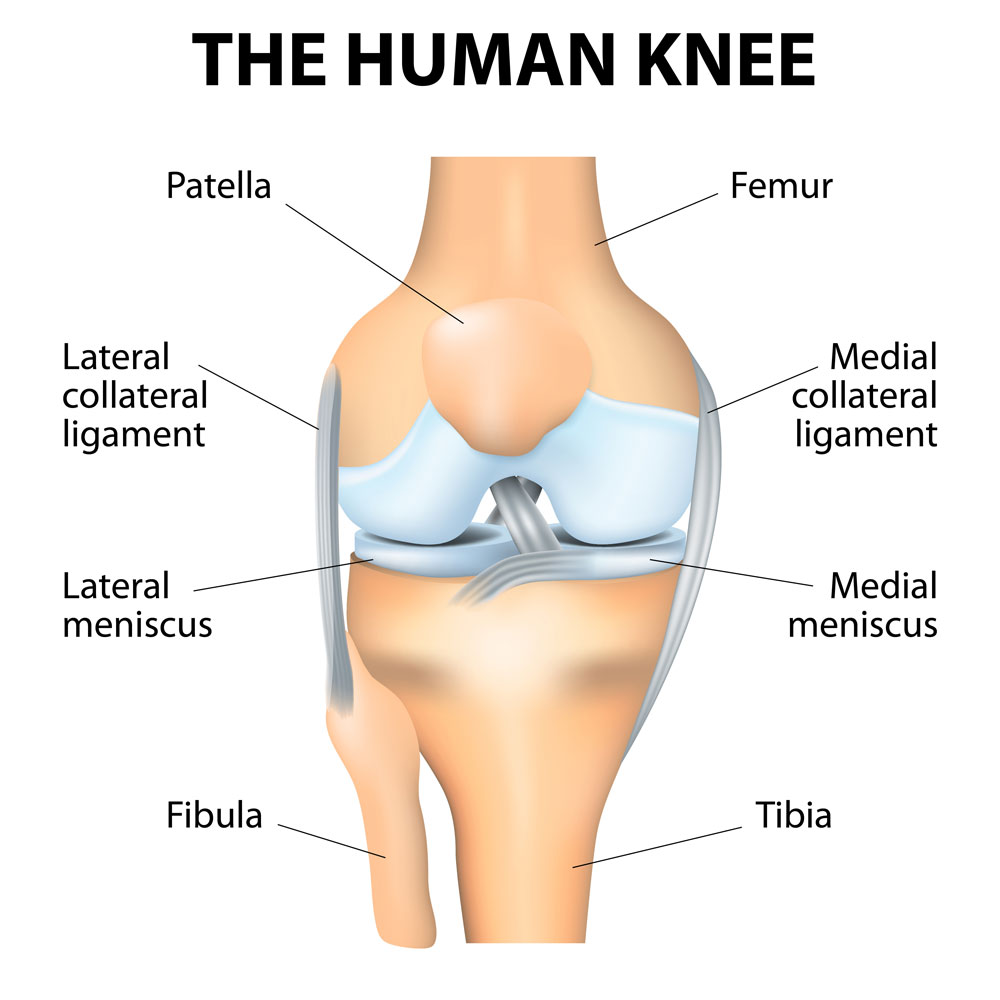

Анатомические изображения менисков и коленного сустава

Раздел: Иллюстрированные советы